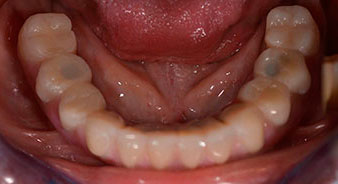

Пациентката е 64-годишна жена с частично обеззъбяване на зъби 38, 33 и 43 и частична долночелюстна протеза (Фиг. 1 и 2).

частично обеззъбяване

Фиг. 1

Фиг. 2